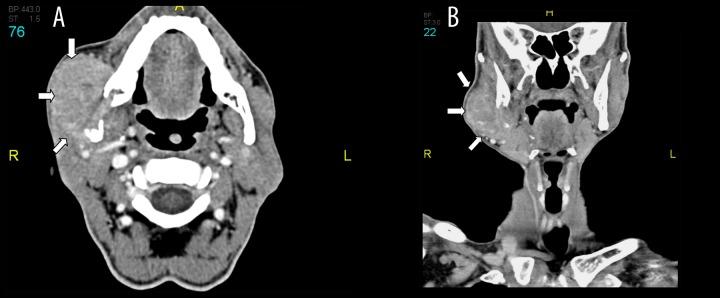

A 66-year-old male with a background of type 2 diabetes mellitus and post-alcoholic decompensated liver cirrhosis presented with a progressively enlarging painful right facial swelling for 2 months that was eventually found to be due to hepatocellular carcinoma metastatic to the right parotid gland. Fine needle aspiration from the right parotid showed sheets and single malignant cells that were interpreted as carcinoma not otherwise specific. However, biopsy showed metastatic hepatocellular carcinoma into the right parotid gland.

一名66岁男性,有2型糖尿病和酒精性失代偿期肝硬化病史,右侧面部逐渐增大的疼痛性肿胀2个月,最终发现是由于肝细胞癌转移至右侧腮腺。右侧腮腺细针穿刺显示成片及单个恶性细胞,诊断为非特异性癌。然而,活检显示为转移性肝细胞癌累及右侧腮腺。